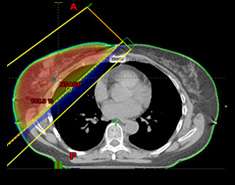

Fig. 1: Whole breast radiation therapy

Whole breast radiation therapy (fig 1)

• Standard fractionation – 6.5 weeks

• Hypofractionation – 3-4 weeks